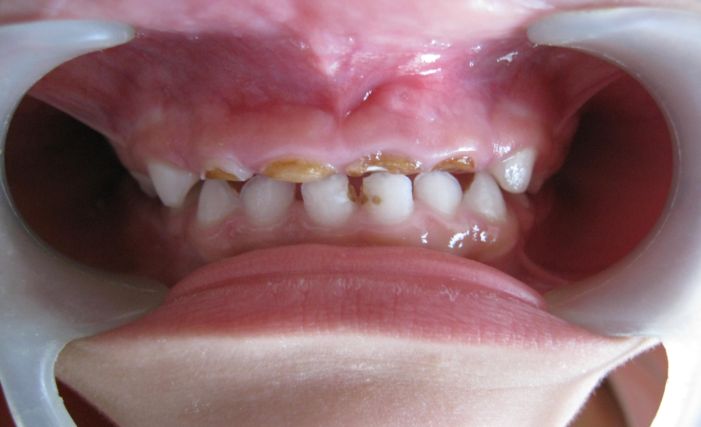

Es una enfermedad que afecta a los niños en sus primeros años de vida y compromete particularmente los dientes de la primera dentición (dientes de leche o dientes temporales) y en algunos casos logra la afectación de los primeros dientes permanentes que empiezan a aparecer hacia los 6 años.

La enfermedad se caracteriza por una destrucción rápida y masiva de estos elementos dentales generando dolor, incapacidad para comer, para hablar para deglutir y si no hay un tratamiento adecuado y a tiempo, los estadios de la enfermedad avanzan y las infecciones se establecen en la cavidad oral y en muchos casos se diseminan a otros sitios de la boca e inclusive de partes del cuerpo diferentes a la cavidad oral.

La causa mas frecuente reconocida de la caries de la infancia temprana es el consumo de carbohidratos contenidos en el biberón con diversos contenidos como leche, jugos, gaseosas, agua de panela, coladas o cualquier otra bebida con alto contenido de azúcar; la leche materna es considerado otro elemento que también produce caries de la infancia temprana.